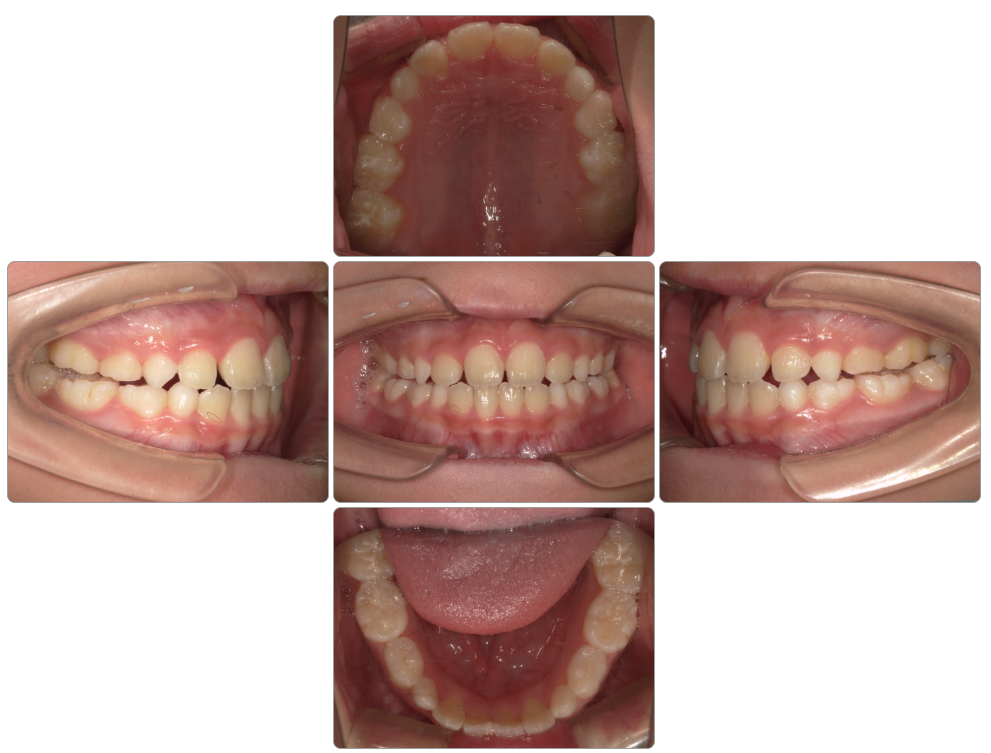

叢生の治療例

Before

after

| 初診時 | 9歳8ヵ月 |

| 治療期間 | 1年半 |

| 費用 | ¥550,000・調整料¥5,500/月 |

| 使用装置 | マイオブレイス |

| リスクと副作用 | |

| 原因と考察 | 頭位が上がった姿勢になっているために舌が口蓋(上顎)に触れていません。このため口蓋の広がりが悪く歯並びが小さくなっているようです。マイオブレイスと共に正しい姿勢で生活できるようになることでその後の後戻りリスクが下がると思います。 |